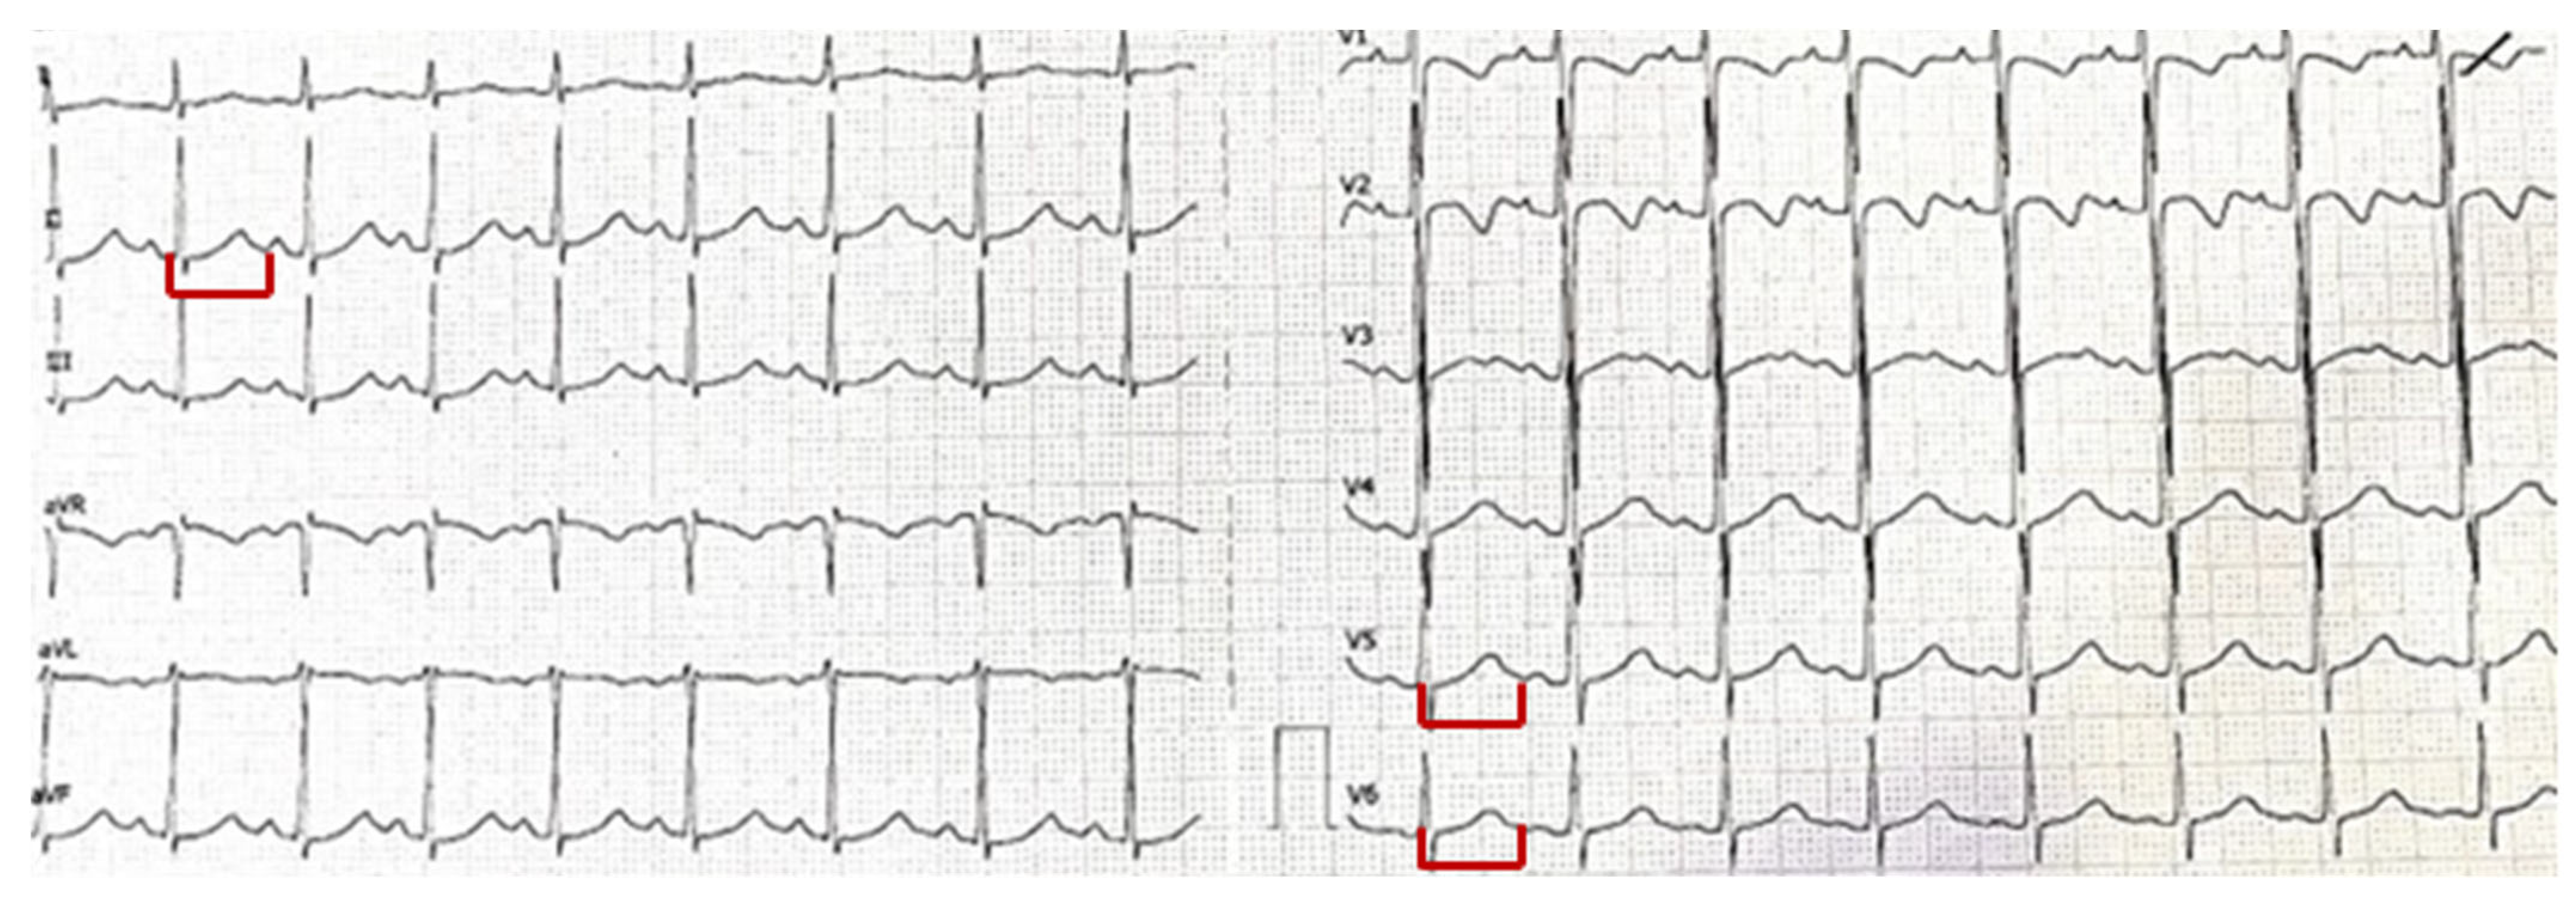

Hyperventilation Syndrome in a Child: Electrolyte Disturbances and Cardiac Involvement in Anxiety-Related Presentations

2. Case Report